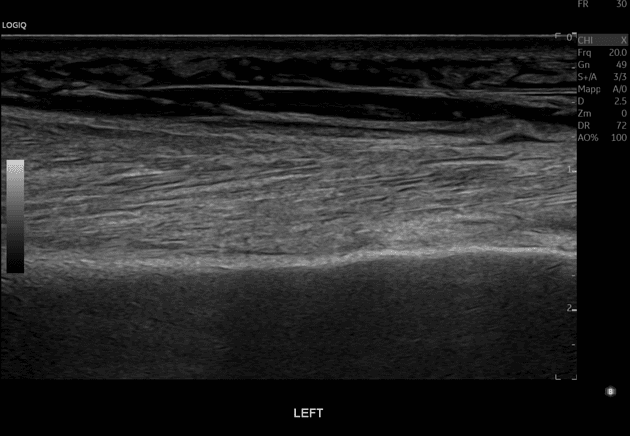

Khó thở và đau ngực 3 tuần sau phẫu thuật thay van động mạch chủ (AVR), siêu âm tim phát hiện khối ở tâm nhĩ trái.

- Tổn thương hình bầu dục ở thành sau tâm nhĩ trái, hướng phát triển ra trước vào trong lòng tâm nhĩ, gây chèn ép tâm nhĩ đáng kể.

- Tổn thương có mật độ thấp (hypodense), đồng nhất (homogeneous), mật độ hơi cao hơn so với các ổ dịch màng ngoài tim nhỏ phía trước.

- Màng ngoài tim không giãn, được thấy tách rời một phần với mặt sau của tổn thương bởi một lớp mỡ bình thường, mỏng.

- Dịch màng ngoài tim hình dạng bất thường, ít lượng, thấy ở phía trước, phù hợp với hình ảnh hậu phẫu mong đợi.

- Tăng quang bình thường của tai tâm nhĩ trái, không thấy hình ảnh huyết khối (no evidence of thrombus).

- Không thấy tắc tĩnh mạch phổi (no pulmonary vein occlusion).

- Van động mạch chủ nhân tạo nằm ở vị trí như mong đợi.

- Ghi nhận dây khâu xương ức (sternotomy wires).

- Ít dịch màng phổi trái và xẹp phổi (atelectasis) mức độ nhẹ ở vùng đáy sau phổi trái.

- Khối máu tụ thành trong (intramural hematoma) tại thành sau tâm nhĩ trái (left atrial posterior wall intramural hematoma).

Khối máu tụ thành trong thành sau tâm nhĩ trái (left atrial posterior wall hematoma)

Bệnh nhân được theo dõi sát bằng siêu âm tim, và khối máu tụ giảm dần về kích thước trước khi bệnh nhân mất theo dõi.